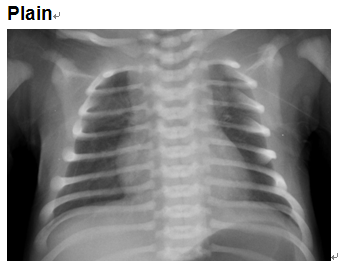

4 months old male infant with cyanosis, Systolic heart mummer in left intercostals' space

Zhao Lei, Beijing Anzhen Hospital